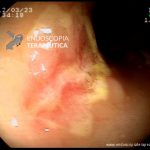

- Doença de Crohn em remissão – pseudopólipo